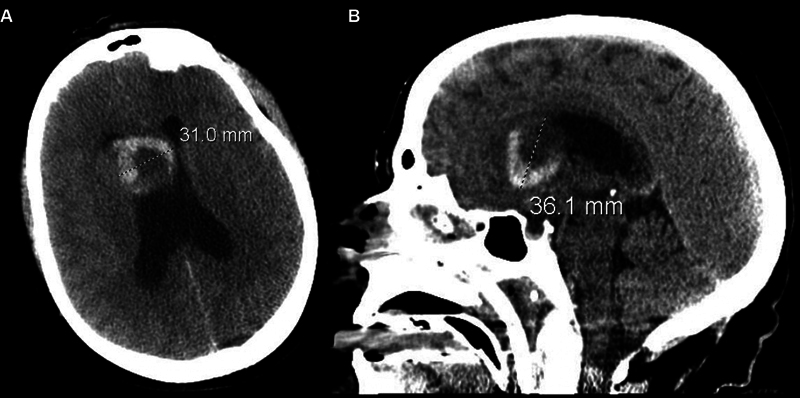

背景:室管膜下巨细胞星形细胞瘤(SEGA)是一种发生于室管膜下组织的罕见肿瘤。SEGA主要与结节性硬化症(TSC)相关,可表现为一系列不同的症状,最常见的是癫痫发作或TSC的神经皮肤特征。我们提出一个新病例散发性SEGA在一个59岁的妇女谁提出了急性肝实质内出血(IPH)。方法系统查阅文献,结合案例分析。结果1例59岁女性患者表现为头痛,意识水平下降,急性IPH累及前隔透明膜和右侧内侧尾状头。MRI提示有潜在的肿瘤,后续影像学显示肿瘤生长缓慢,需显微手术切除。术后病理证实SEGA (WHO I级),无TSC1/2突变。随访1年,患者无疾病,神经功能完整。一项系统综述确定了7篇出版物,在9名无TSC的成年患者中病理证实了SEGA。头痛、乳头水肿和视觉障碍是最常见的症状。治疗方案包括显微手术切除与活检后的放射学监测,截至最后一次随访,总体无症状生存率至少为80%。结论:我们报告了第10例散发性SEGA成人患者,无TSC,并对这种罕见的肿瘤实体进行了相关的系统回顾。需要进一步的研究来确定散发性SEGA发展的危险因素,以及可能偏离儿童TSC患者标准方案的这种疾病管理的潜在途径。

Background  Subependymal giant cell astrocytoma (SEGA) is a rare neoplasm arising from subependymal tissue. Predominantly associated with the tuberous sclerosis complex (TSC), SEGA may present with a range of diverse symptoms, most commonly seizures or neurocutaneous features of TSC. We present a novel case of sporadic SEGA in a 59-year-old woman who presented with acute intraparenchymal hemorrhage (IPH). Methods  Systematic literature review and illustrative case example. Results  A 59-year-old woman presented with a headache decreased level of consciousness, and acute IPH involving the anterior septum pellucidum and right medial caudate head. MRI was concerning for an underlying neoplasm, which grew slowly on follow-up imaging, prompting microsurgical resection. A gross total resection was achieved, and postoperative pathology confirmed SEGA (WHO grade I) without TSC1/2 mutation. She remained disease-free and neurologically intact at 1-year follow-up. A systematic review identified seven publications that revealed pathologically confirmed SEGA in nine adult patients without TSC. Headache, papilledema, and visual disturbances were the most common presenting symptoms. Treatment protocols included microsurgical resection versus biopsy followed by radiographic surveillance, and the overall rate of symptom-free survival was at least 80% as of the last follow-up. Conclusion  We report the tenth case of sporadic SEGA in an adult patient without TSC, as well as an associated systematic review of this rare neoplastic entity. Further study is required to identify risk factors for the development of sporadic SEGA, as well as potential avenues for the management of this disease that may depart from the standard protocol in pediatric TSC patients.